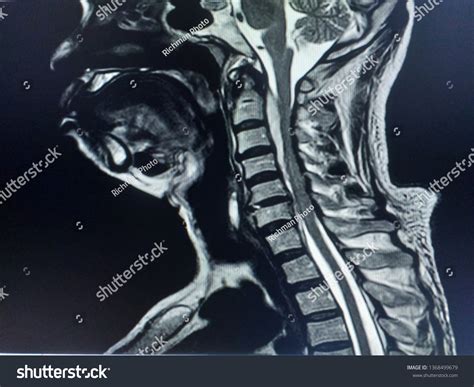

• normal cervical mri sagittal view